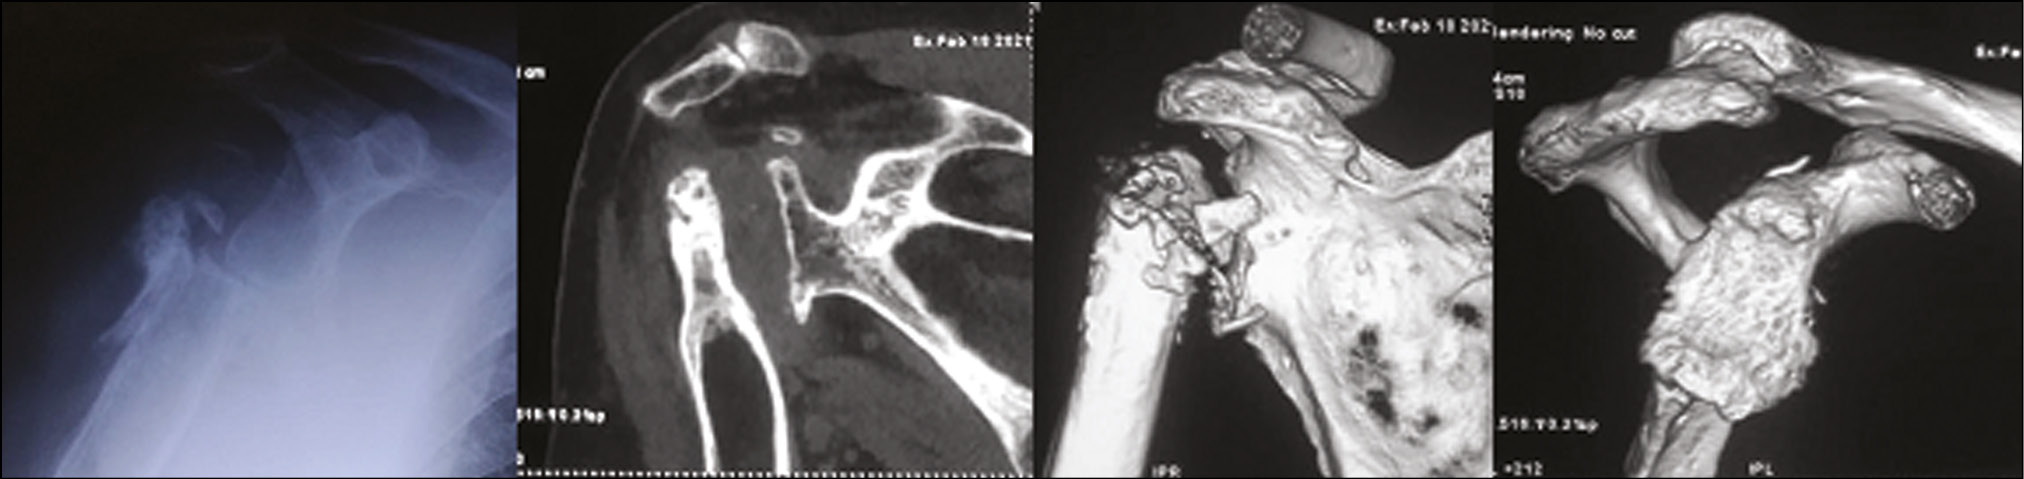

The patient had a history of gunshot injury in the right shoulder joint more than 15 years ago and had repeated reconstructive surgery on the shoulder joint. X-ray imaging and CT revealed post-traumatic arthrosis of the right shoulder joint with pronounced “wear” and medialization of the glenoid and a defect in the proximal humerus (Fig. 4).

Fig. 4. Patient S., 75 years old. X-ray picture